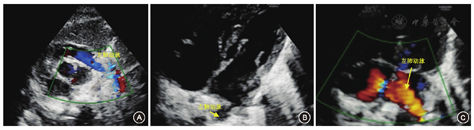

转入后体格检查:体温36.2℃、心率150次/min,呼吸48次/min,血压62/27 mmHg(1 mmHg=0.133 kPa),平均动脉压40 mmHg;足月儿貌,反应可,哭声响亮,全身皮肤无黄染;唇无发绀,颈软,未见三凹征,左肺可闻及散在湿啰音,右肺未闻及明显呼吸音。入院诊断:(1)新生儿肺炎;(2)先天性右肺缺如?;(3)心包积液?。予以抗感染、预防出血鼻导管吸氧等处理。该患儿鼻导管给氧2 h,呼吸一直平稳,各项生命体征指标正常。生后2 d患儿胸部X射线片提示:右侧胸腔呈密度均匀致密影;左肺野透亮度增高,纵隔心影向右移位,右膈肌面显示不清,左膈肌面光滑,左肋膈角锐利。生后3 d行胸部CT扫描,在三个维度均显示右肺未发育(图3);诊断:先天性右肺缺如。超声心动图:心脏大部分位于右侧胸腔,心尖朝左;主动脉根部内径宽9 mm,左心房10 mm,左心室15 mm,室间隔厚3 mm,左心室后壁厚3 mm,右心房12 mm,右心室12 mm,肺动脉8 mm,左肺动脉内径3 mm;右肺动脉、静脉未显示,肺动脉峰值流速0.7 m/s;主动脉峰值流速1.1 m/s;二尖瓣:左心室舒张早期快速充盈的充盈峰(E峰)0.8 m/s,舒张晚期(心房收缩)充盈的充盈峰(A峰)0.7 m/s,E峰>A峰,左心室缩短分数40%,射血分数65%;心脏各房室内径大小正常,房间隔可见宽2.5 mm的连续中断,室间隔探及宽1.6 mm的穿隔血流信号,室间隔与左心室后壁运动正常;各瓣膜清晰,启闭正常,升主动脉、肺动脉位置和内径正常,降主动脉与肺动脉分叉处可见交通支,心包腔内未见明显异常回声(图4)。

注:R:右侧(Right)